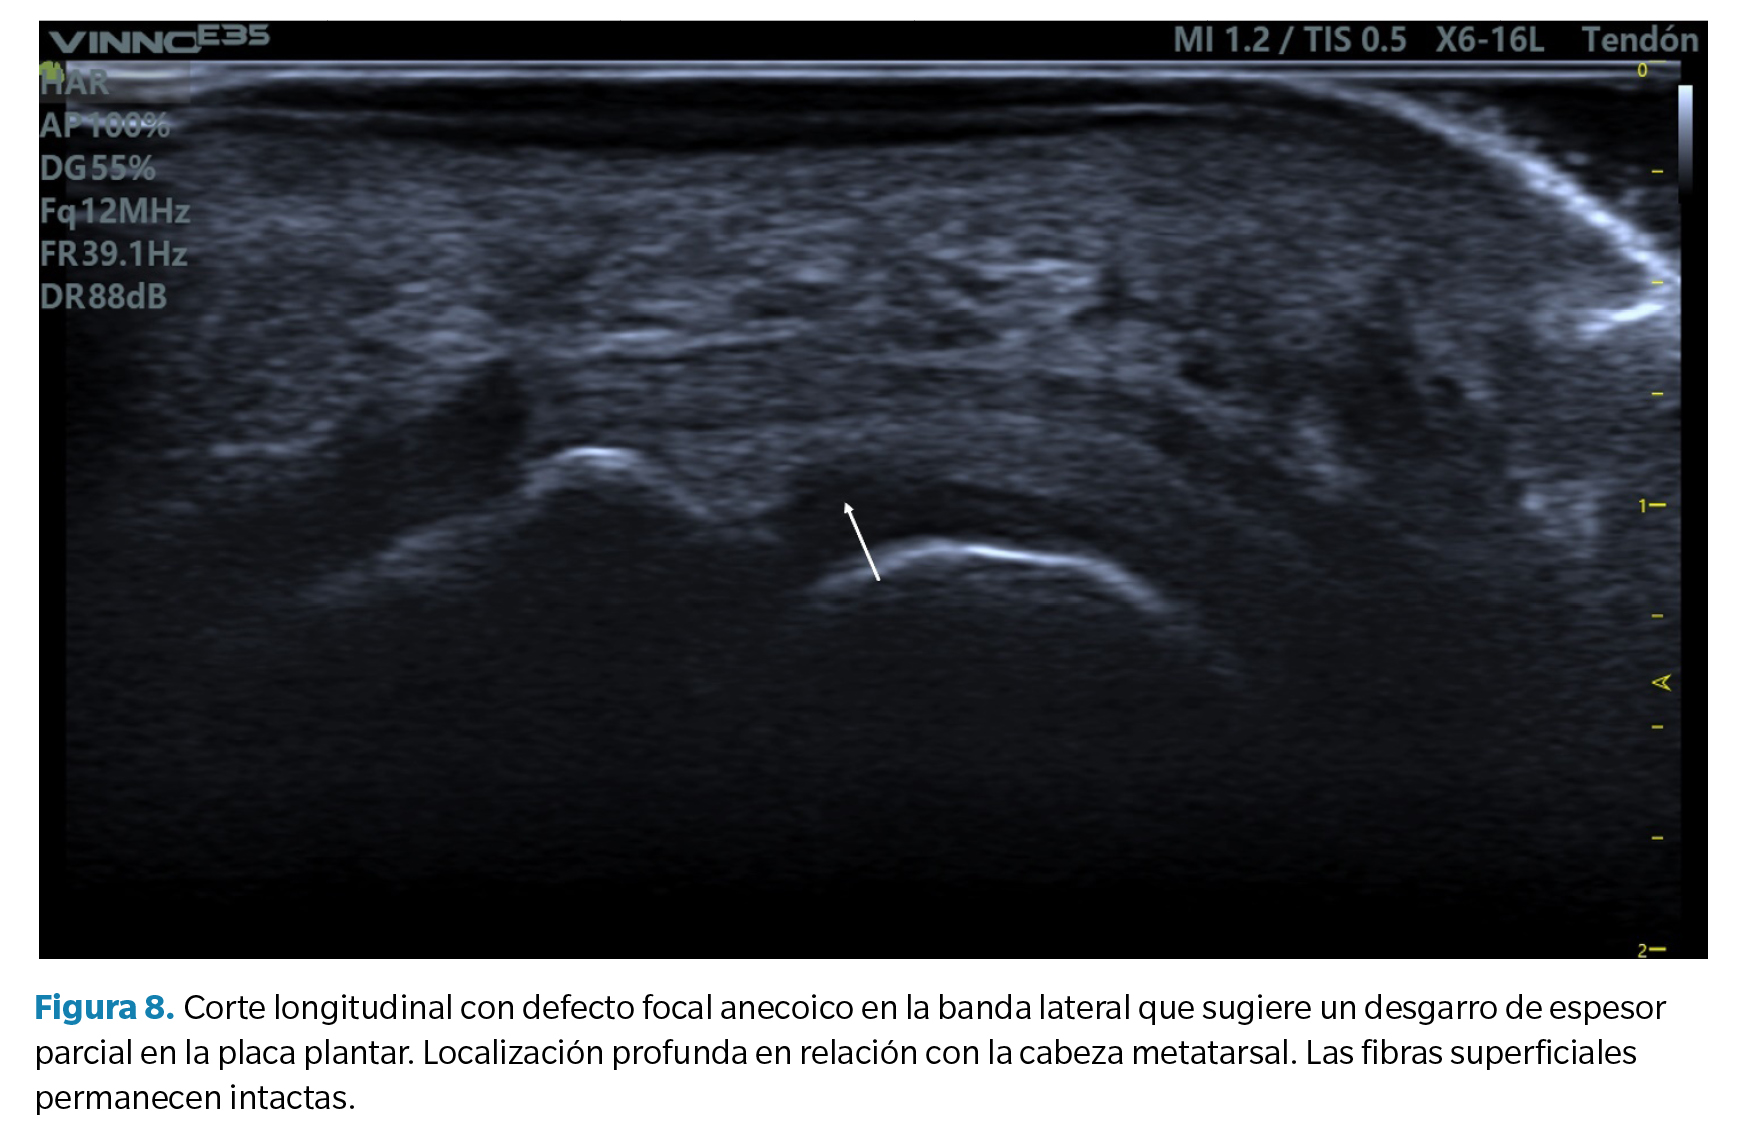

- Defecto focal anecoico o hipoecoico. Se aprecian como una hendidura discreta en la zona profunda del tejido (zona que articula con la cabeza metatarsal) en su margen lateral. Cuando las fibras superficiales están intactas hablamos de un desgarro de espesor parcial, mientras que cuando dicho desgarro atraviesa todo el tejido hasta su región superficial hablamos de un desgarro de espesor total39 (Figura 8).

Como se ha señalado, en todos los casos las maniobras dinámicas de tensión del dedo (y la placa) son esenciales para establecer la presencia o no de un desgarro y su magnitud41,42. La incapacidad de tensar la placa (pasar de su estado curvado a un estado lineal) así como la pérdida de movimiento congruente entre la falange proximal y la placa son signos muy sugerentes de desgarro que solo pueden apreciarse mediante dichas maniobras.